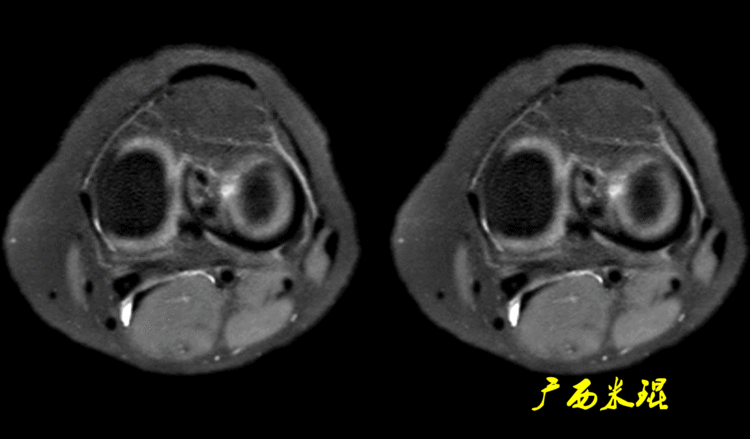

12、半月板外周血管半月板的血供来自于膝下内侧动脉、膝下外侧动脉、膝中动脉、膝上内侧动脉(膝上外侧动脉不参与半月板血供!)、膝降动脉、膝后内侧动脉和膝后外侧动脉,以上这些动脉形成紧绕半月板的周围动脉环。

膝下内侧动脉自后向前经胫骨内侧缘与腘肌上缘的筋膜内走向前侧,至胫骨内侧缘前下方沿内侧半月板外周走行,MR造影下显示血管其实是非常清楚的,大部分的医院不愿意花费太多的时间而已。

膝下外侧动脉在距腓骨小头顶点上方,经腓侧副韧带深面,紧贴外侧半月板外周向前走行,MR上容易将其误认为半月板边缘分离。

膝下内侧动脉、膝下外侧动脉等共同组成血管环,MR轴位上也常常被误诊为半月板关节囊分离,其实两者完全不同。

半月板的血管走向并不是恒定不变的,可能会变异,加之扫描体位参数的不同等,部分截面的血管影容易误认为是半月板3级信号。